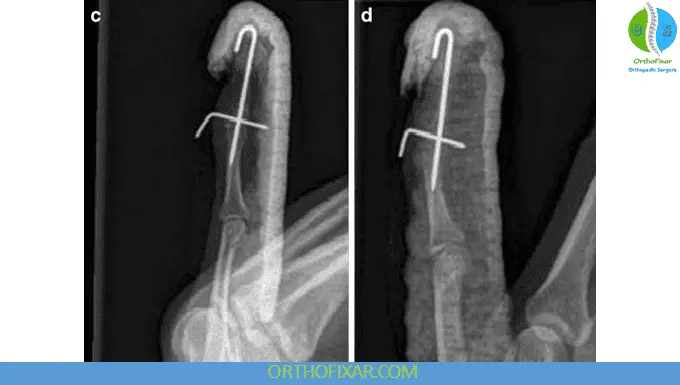

2. Surgical Treatment

Surgery is reserved for specific indications:

Indications

- Open injuries

- Large bony fragment (>30–50% joint surface)

- DIP joint subluxation

- Failed conservative treatment

- Chronic deformity with functional deficit

Surgical Options

- Kirschner wire fixation

- Extension block pinning

- Screw fixation

- Tendon reconstruction